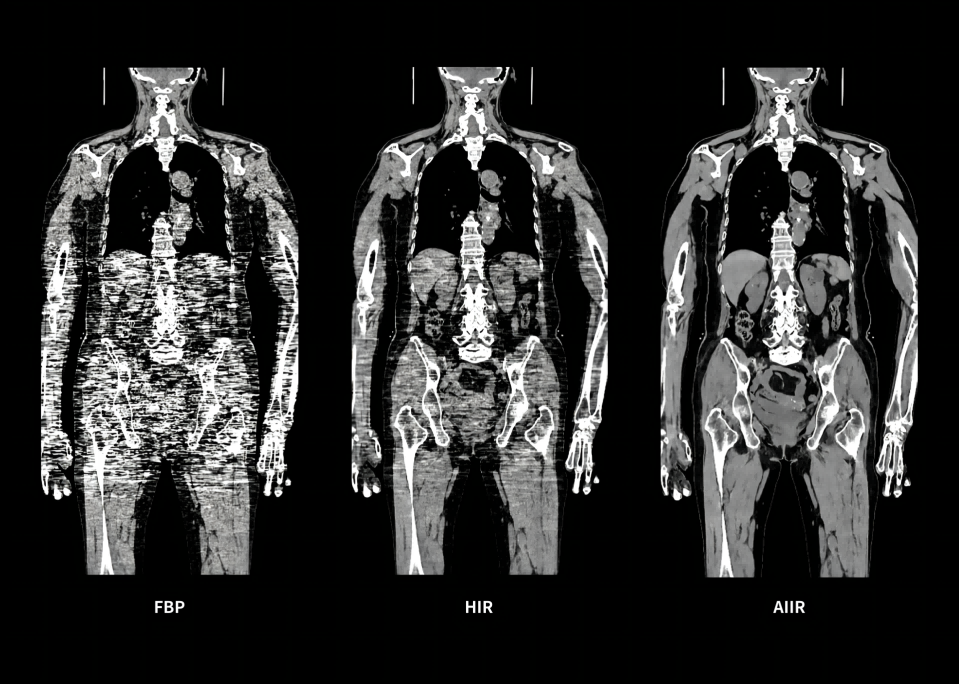

Throughout the iterative loop of forward and backward projection between the raw data domain and the image domain, AIIR consistently takes into account the accurate modeling of optics, noise, anatomy, and physics statistics. Additionally, AIIR integrates deep learning-based de-noising technology, supplanting the conventional regularization role of MBIR in the optimization reconstruction process.

In brief, AIIR utilizes deep learning-based AI technology to attain robust noise reduction and natural image texture, while incorporating MBIR technology to achieve precise anatomical structure representation and artifact suppression. This technique surpasses the limitations of using either MBIR or deep learning reconstruction (DLR) independently.